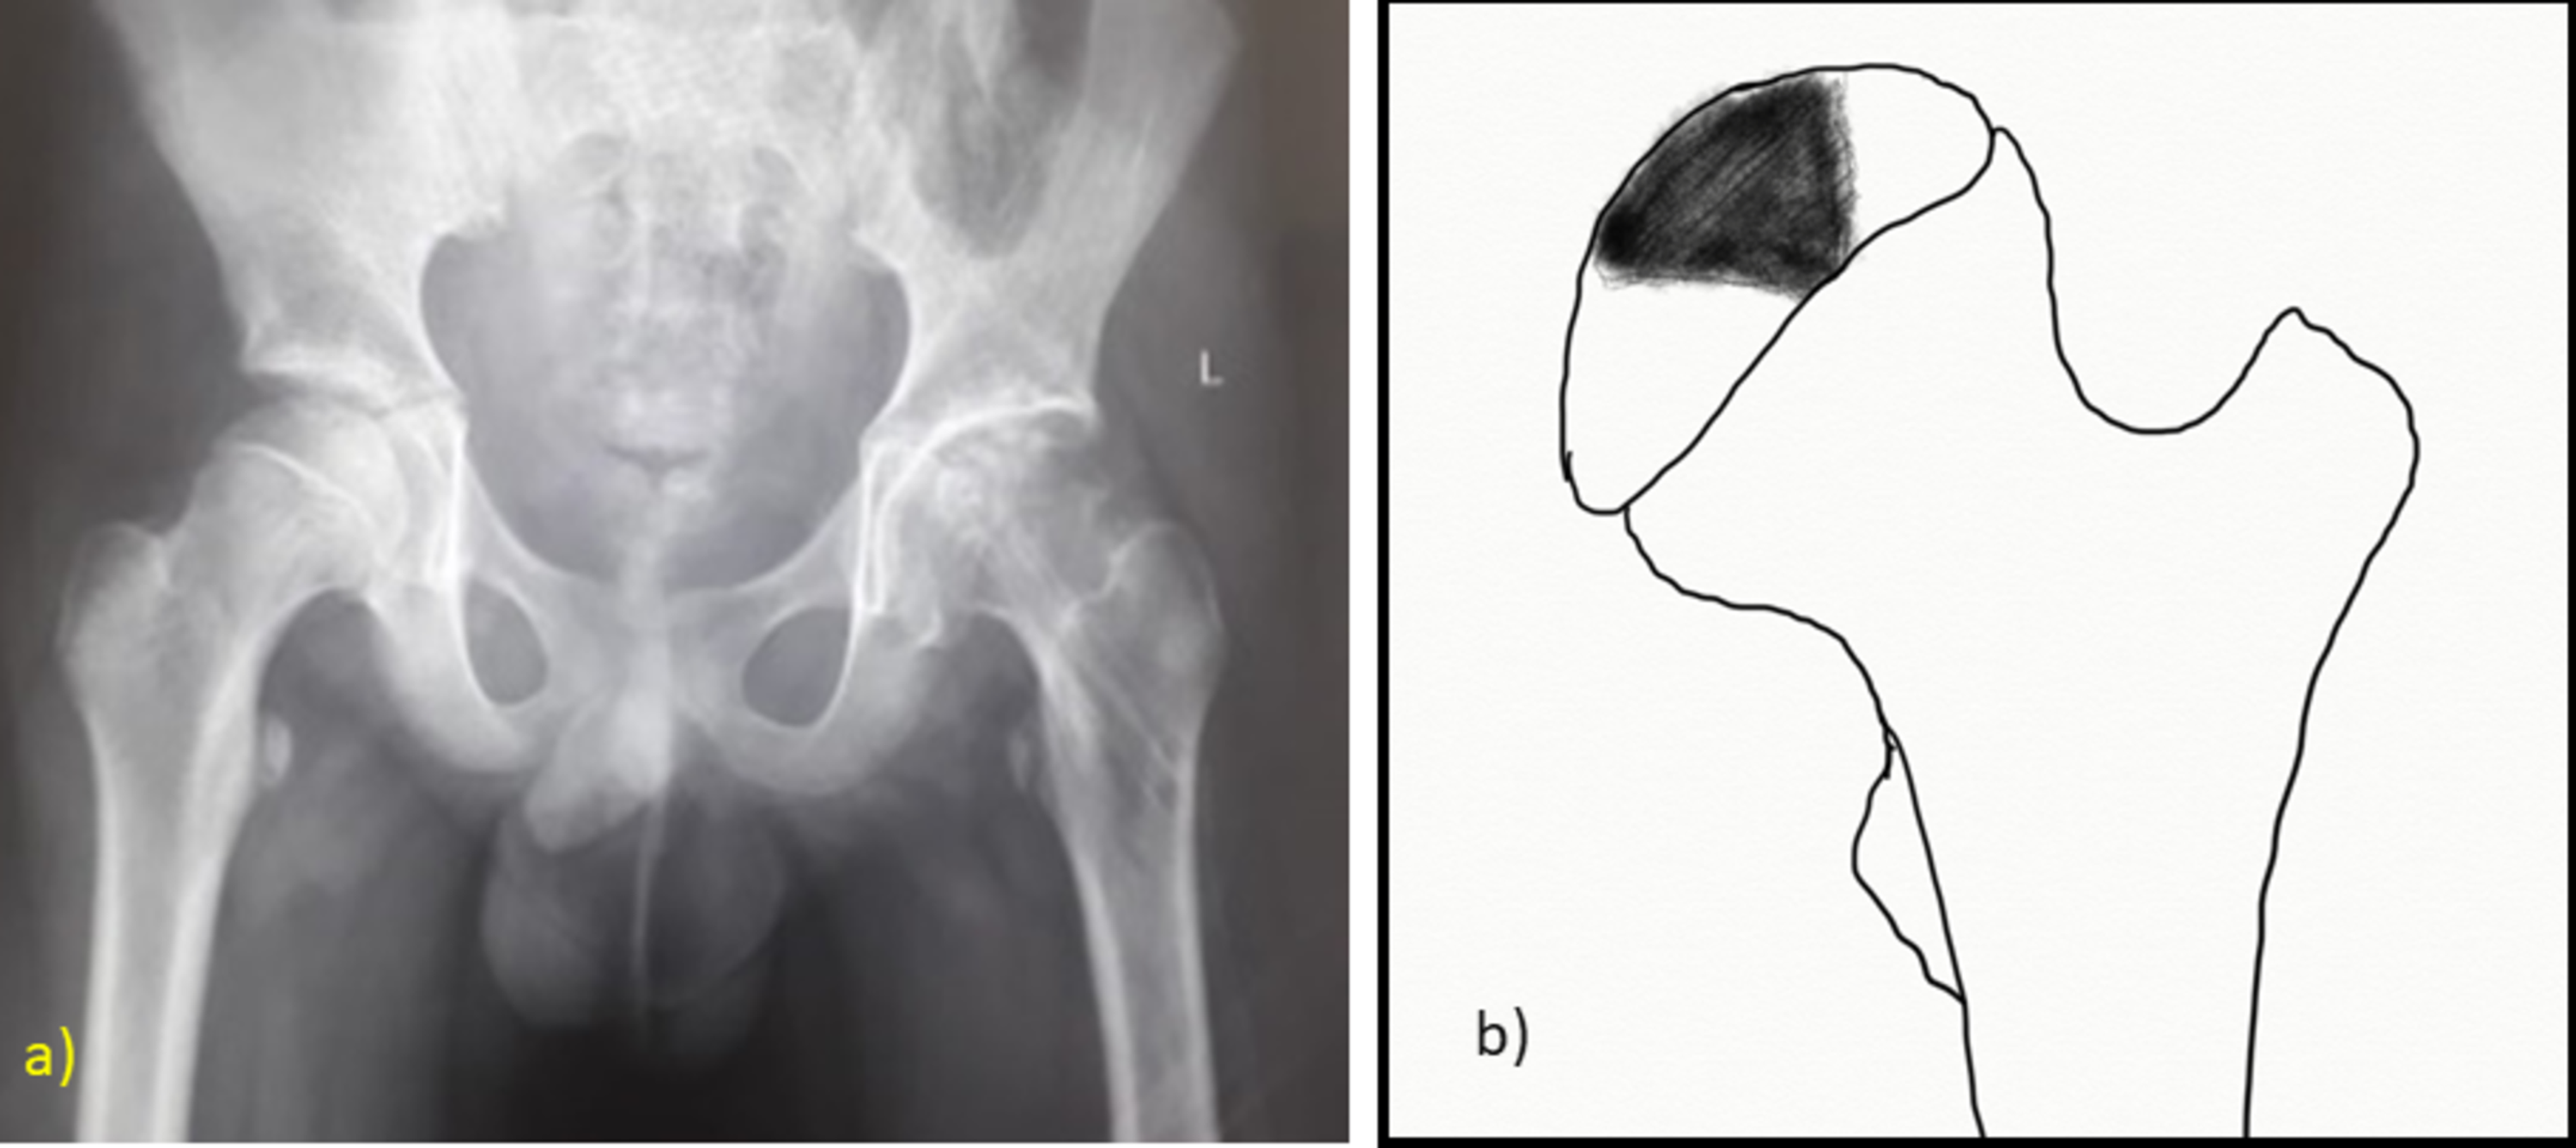

Avascular Necrosis of the Femoral Head Diagnosis Sports Medicine Review

Avascular Necrosis of the Femoral Head Diagnosis Sports Medicine Review What Is Avascular Necrosis Of The Femoral Head Avascular necrosis (an) of the femoral head is a pathologic process that results from interruption of blood supply to the bone. More than 20,000 people each. Femoral head ischaemia causes bone marrow and. Although it can occur in any bone, osteonecrosis most commonly affects the hip. Hip osteonecrosis, also known as avascular necrosis of the hip, represents a condition caused. What Is Avascular Necrosis Of The Femoral Head.

Avascular Necrosis (AVN) of the Femoral Head Findings on XRay What Is Avascular Necrosis Of The Femoral Head More than 20,000 people each. Hip osteonecrosis, also known as avascular necrosis of the hip, represents a condition caused by reduced blood flow to the femoral head secondary to a variety of risk factors such as. Osteonecrosis is also called avascular necrosis (avn) or aseptic necrosis. Femoral head ischaemia causes bone marrow and. Osteonecrosis of the femoral head, previously known. What Is Avascular Necrosis Of The Femoral Head.